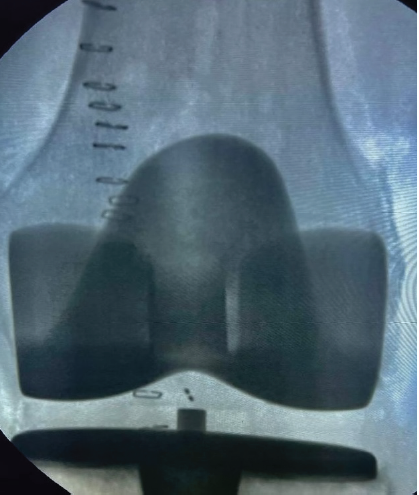

As per institutional protocol, drain removal was attempted after 24 h of surgery. Despite a moderate traction force, the drain could not be withdrawn. Repositioning the knee into flexion was attempted, but this resulted in the drain breakage with retention of the proximal segment. An investigation was undertaken to determine the cause. Post-operative radiographs of the knee failed to clearly demonstrate the retained drain (Fig. 1).

Figure 1: Anteroposterior radiograph of the knee in the post-operative period.